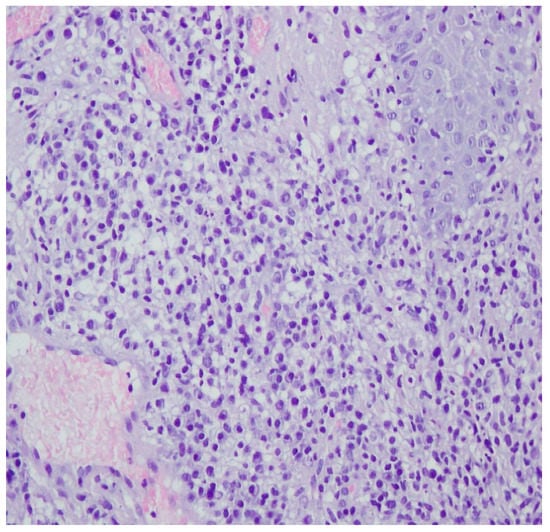

A revision of the biopsy from September 2021 showed a thickened epidermis and lymphocytic and histiocytic inflammatory infiltration with multiple plasmacytes (Figure 10 and Figure 11).

Figure 10.

Thickened epidermis. Lymphocytic and histiocytic inflammatory infiltration with multiple plasmacytes. Histopathological picture and data from the history are consistent with syphilis.

Figure 11.